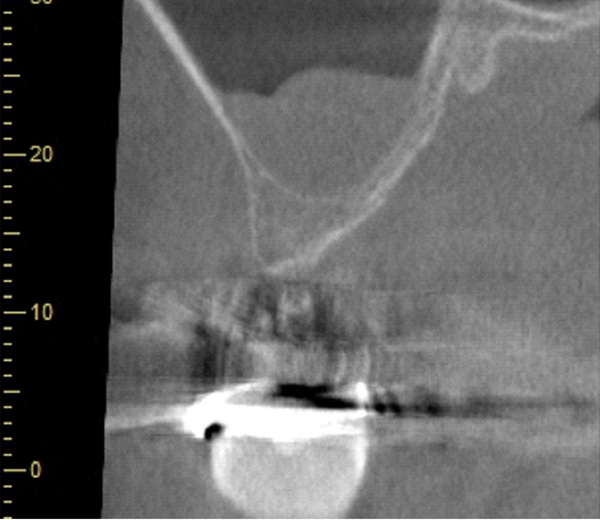

| 年代・性別 | 50代 男性 |

|---|---|

| 主訴 | 前医で前歯を抜かなければならないがインプラントはできないと言われた |

| 治療期間 | 約12ヶ月 |

| 費用 | 600,000円 |

| 治療内容 | インプラント、骨造成、結合組織移植、セラミック修復 |

| 治療に伴うリスク | インプラント周囲炎 セラミックの破折、脱離 |